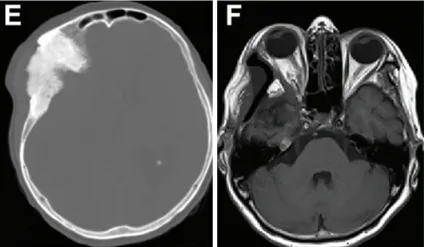

术前轴位计算机断层扫描,显示反应性骨质增生及肿瘤累及骨骼的范围(图E)。术后MRI(图F)显示眼球突出显著改善(眼球突出指数=1.11)。